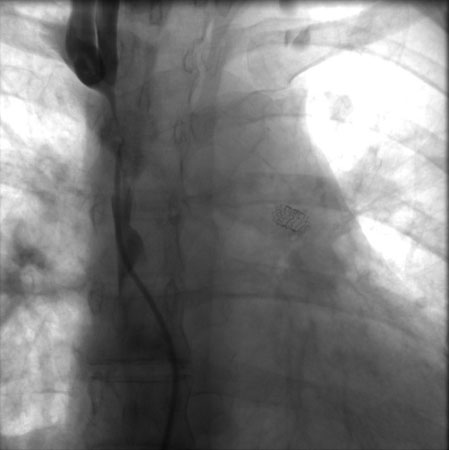

Done percutaneously by obtaining access usually through the femoral vein. Performed under conscious sedation. Fluoroscopic guidance and iodinated contrast are used. Most operators use heparin during the procedure. [Figure caption and citation for the preceding image starts]: Postdilatation of the superior vena cava stentImage obtained from cardiac catheterization laboratory at University of Missouri, Columbia; used with permission [Citation ends].[Figure caption and citation for the preceding image starts]: Venography showing superior vena cava stenosis. Stent placement in the left pulmonary artery is seenImage obtained from cardiac catheterization laboratory at University of Missouri, Columbia; used with permission [Citation ends].

[Figure caption and citation for the preceding image starts]: Percutaneous balloon angioplasty of the stenotic lesion in superior vena cavaImage obtained from cardiac catheterization laboratory at University of Missouri, Columbia; used with permission [Citation ends].

Undertaken percutaneously by obtaining access (usually) through the femoral vein. Performed under conscious sedation. Fluoroscopic guidance and iodinated contrast are used and most operators use heparin during the procedure.[Figure caption and citation for the preceding image starts]: Postdilatation of the superior vena cava stentImage obtained from cardiac catheterization laboratory at University of Missouri, Columbia; used with permission [Citation ends].[Figure caption and citation for the preceding image starts]: Venography showing superior vena cava stenosis. Stent placement in the left pulmonary artery is seenImage obtained from cardiac catheterization laboratory at University of Missouri, Columbia; used with permission [Citation ends].